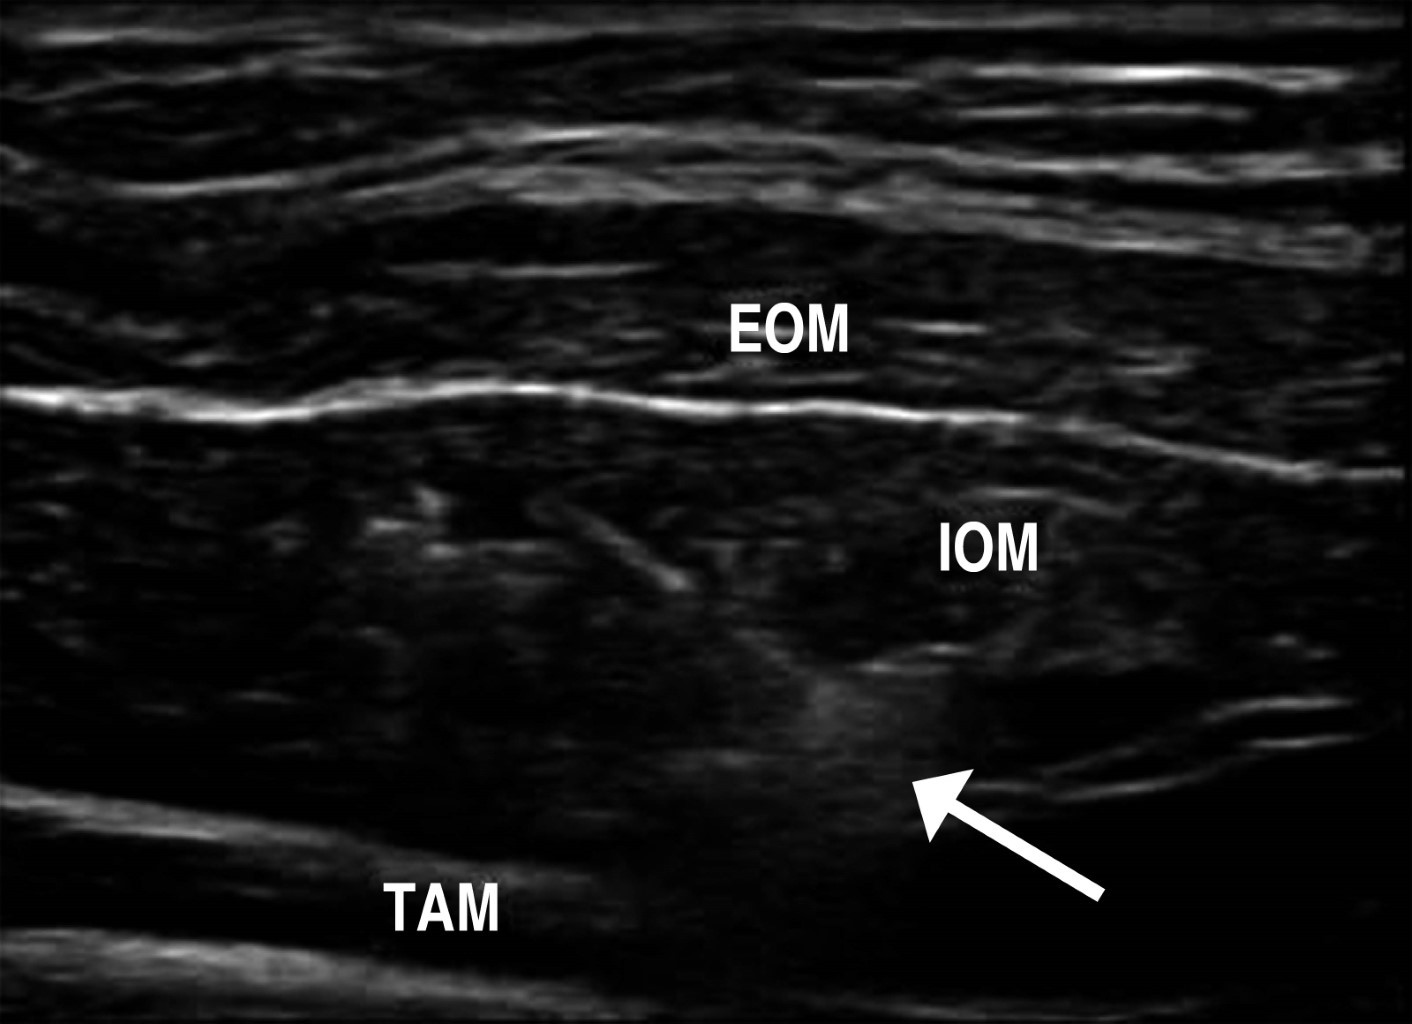

THERAPEUTIC ULTRASOUND OF THE ABDOMINAL WALL

With the aid of a portable ultrasound equipment, it is feasible to perform anesthetic blocks in the operating room that contribute to reducing postoperative pain and even allow some procedures such as open inguinal plasty under local anesthesia and sedation, umbilical hernia plasty, and midline plasty. The transversus abdominis plane block30 is used by placing the transducer on the flank in an axial plane at the midpoint of the distance between the iliac crest and the inferior costal border. The image of the lateral component muscles is identified with the transducer and, using a dilution of bupivacaine or ropivacaine; the needle is introduced under sonographic guidance until penetration of the two oblique muscles is achieved and infiltrated just between the internal oblique and the transversus abdominis muscle (Figure 8). This procedure produces a block spanning the T9 to L1 dermatomes. Its leading utility is reducing postoperative pain; therefore, it can be applied in all abdominal surgery.

Additionally, for a greater analgesic/anesthetic effect, a rectus sheath block is performed by placing the transducer axially at the level of the epigastrium, at the lateral border of each rectus muscle and infiltrating in front of the posterior aponeurotic sheath. The bilateral combination of these two procedures (bilateral transverse plane and bilateral rectus sheath block) can be used in all abdominal surgery, significantly reducing postoperative pain. In open inguinal plasty, the ilioinguinal and iliohypogastric nerve blocks, plus local anesthesia at the incision site, are used. All these procedures can also be used in the office setting to treat groin or abdominal wall pain in patients with chronic postoperative pain problems or sports injuries by combining the local anesthetic with injectable water and a depot steroid such as 5 mg betamethasone. They may benefit from repeated blocks at 15-day intervals (without necessarily repeating the combined steroid at each block). In the case of botulinum toxin infiltration, as part of preoperative preparation for complex hernia31 the same technique of sonographic guidance is applied in the axial plane of the abdominal flank to inject the toxin, under direct vision of the muscles of the lateral abdominal component. In this case, ultrasound guidance is used by applying five punctures per flank to ensure that the toxin is deposited mainly at the level of the internal oblique muscle.